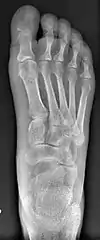

Syndesmosis procedure addresses specifically the two fundamental problems of metatarsus primus varus deformity that gives rise to the bunion deformity. They are leaning and instability of the first metatarsal bone . Syndesmosis procedure uprights the leaning first metatarsal bone with strong binding sutures between it and the second metatarsal bone (Fig. 2) and then also stabilizes it uniquely by creating a fibrous connecting bridge between these two bones (Fig. 3, 4). First metatarsal bone can be readily realigned because by definition of the metatarsus primus varus deformity its first metatarsal is abnormally loose and mobile.

The surgical technique of syndesmosis procedure originated from the osteodesis procedure that was first described by Botteri in 1961.[6] It has since been studied and reported by Pagella in 1971,[7] Irwin in 1999[8] and Wu in 2007.[2] Syndesmosis itself is a normal anatomical structure for the purpose of connecting two parallel long bones side by side, such as the tibia and fibula bones. The naming of syndesmosis procedure was thus to reflect the essence of the technique which is to create a “syndesmosis” mechanism to provide permanent stability to the first metatarsal to prevent recurrence. Both the bone-binding-sutures and syndesmosis-connection concepts are unique and revolutionary in a world of bunion surgery overwhelmingly dominated by osteotomy (bone-breaking) tradition.